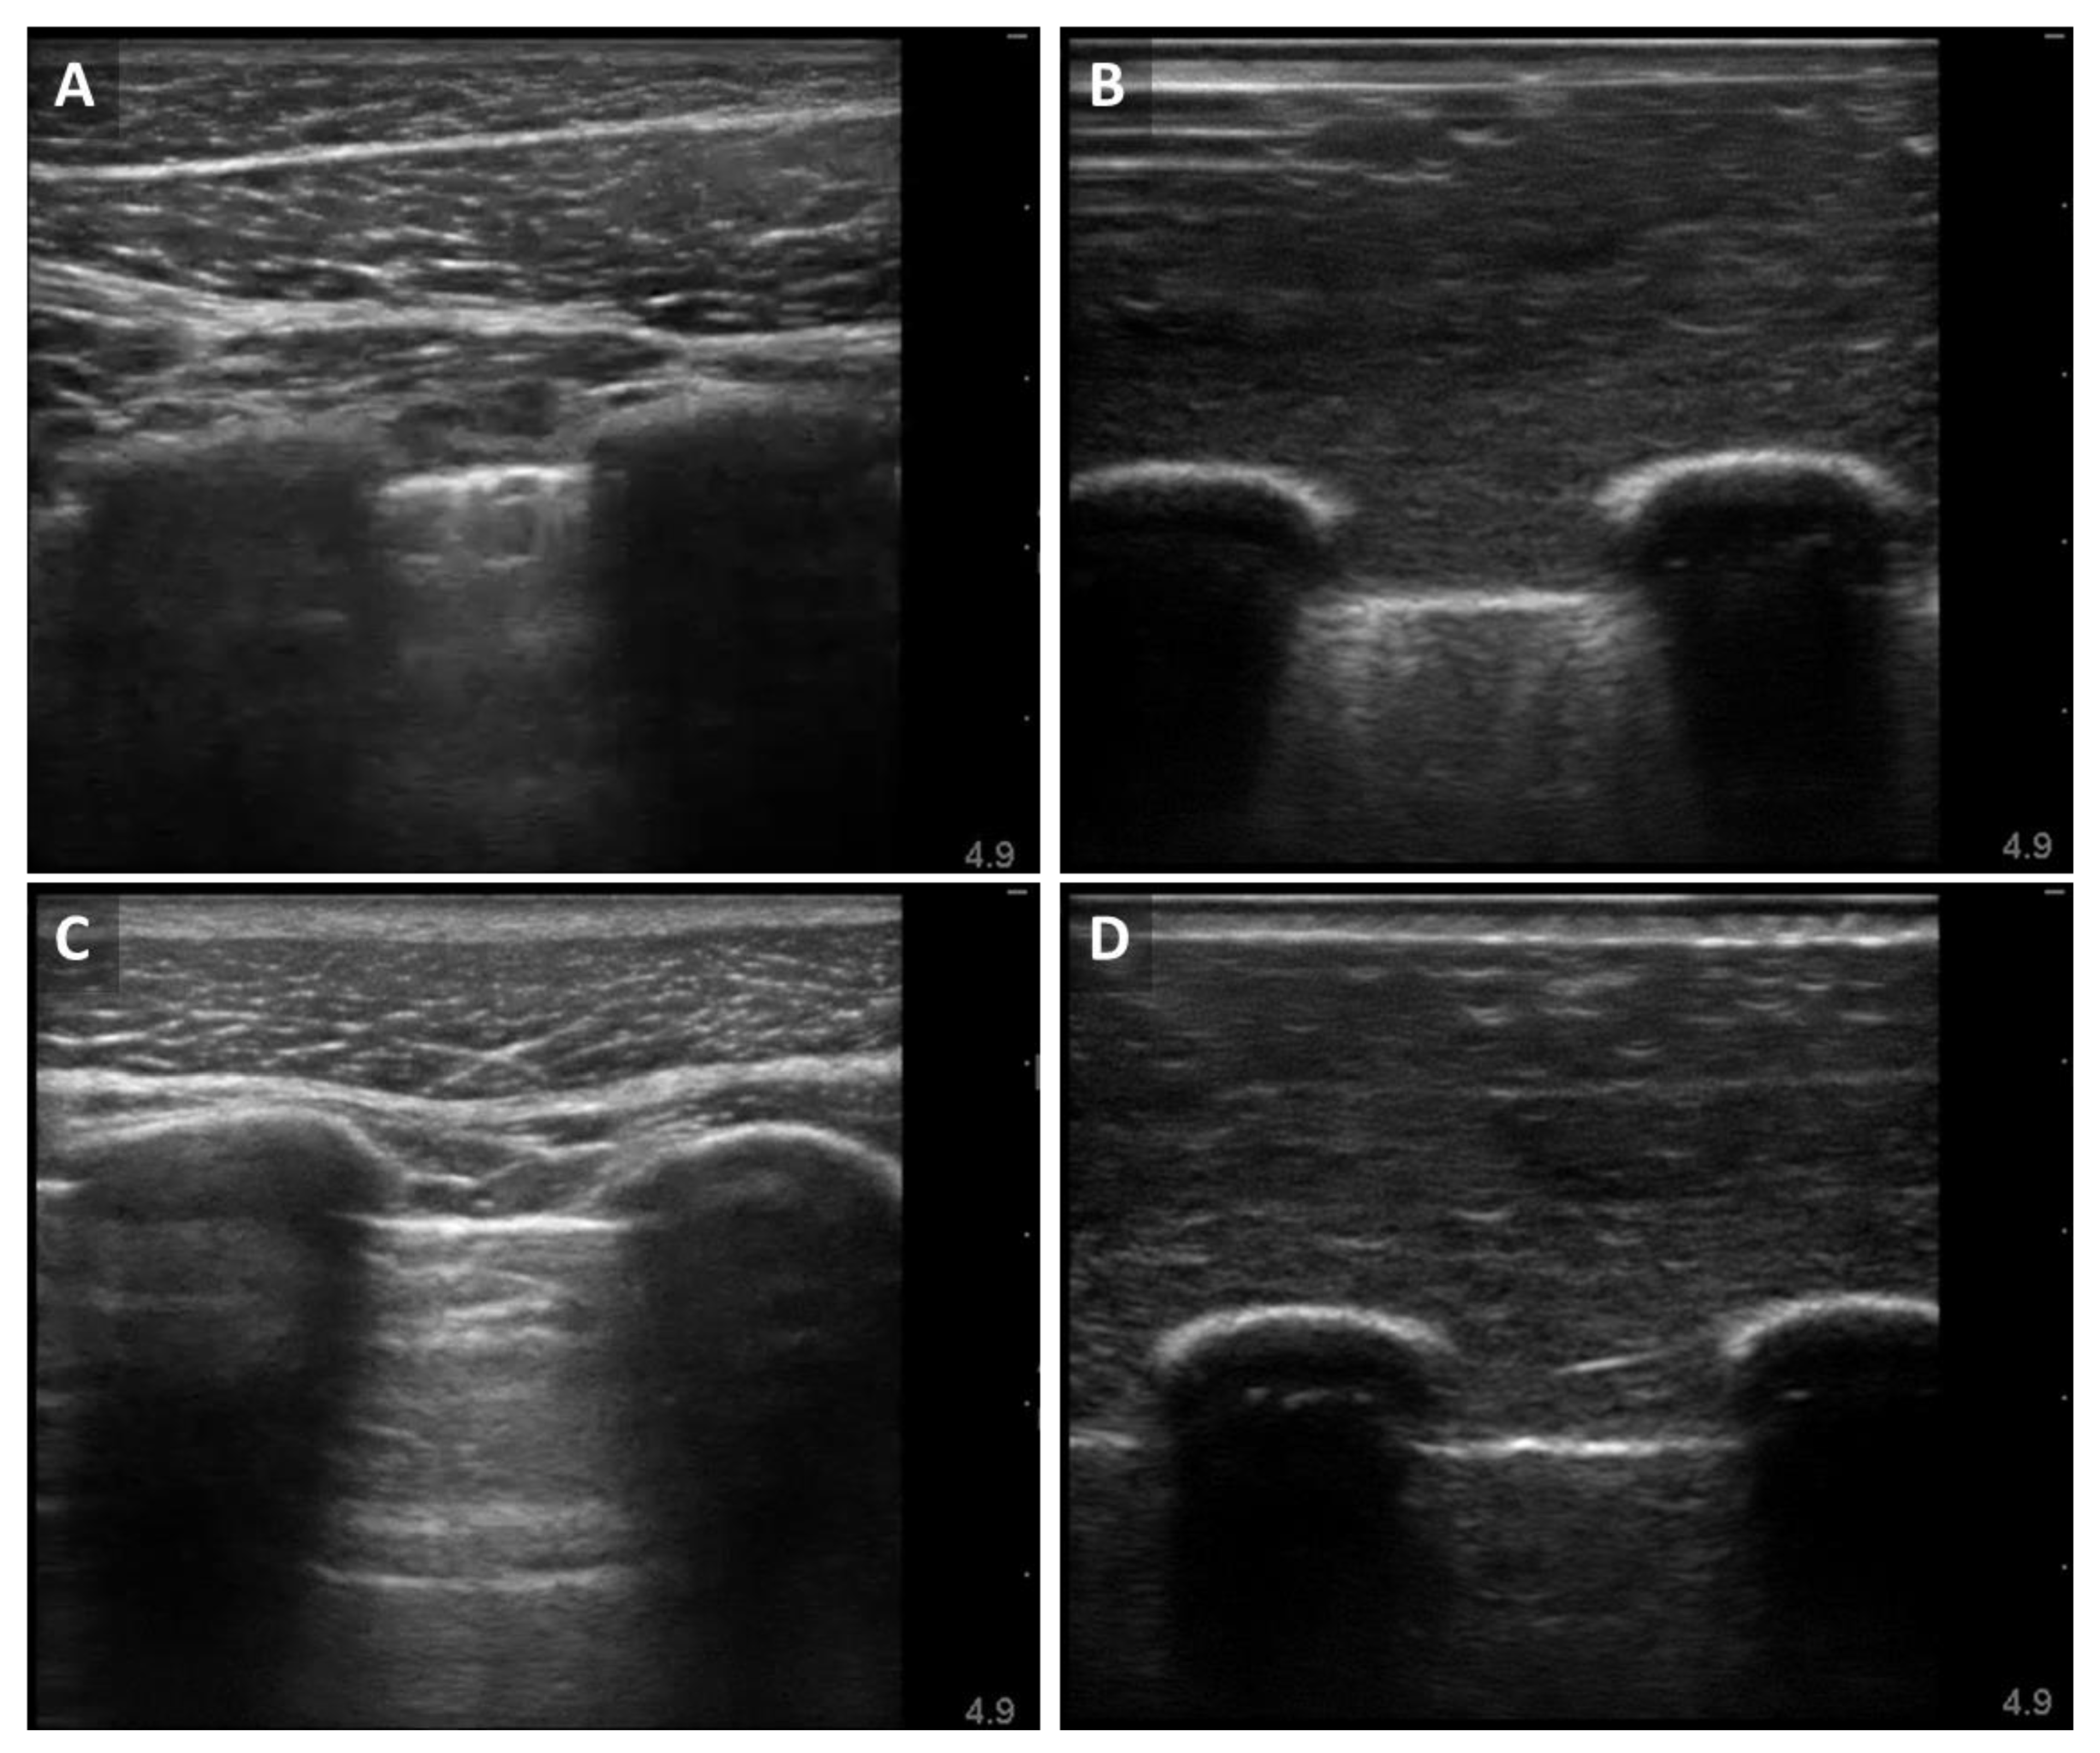

3.1. Ultrasound B-Mode Image Results for the Synthetic Phantom Apparatus

3.2. M-Mode Comparison of Porcine and Synthetic Platforms